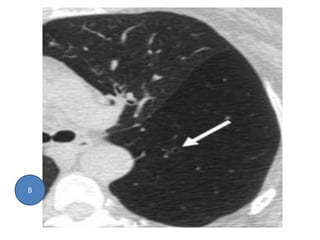

Focal bronchiectasis (idiopathic) in left lower lobe (arrow).

A

Focal bronchiectasis (idiopathic)in left lower lobe (arrow). A

• 47.